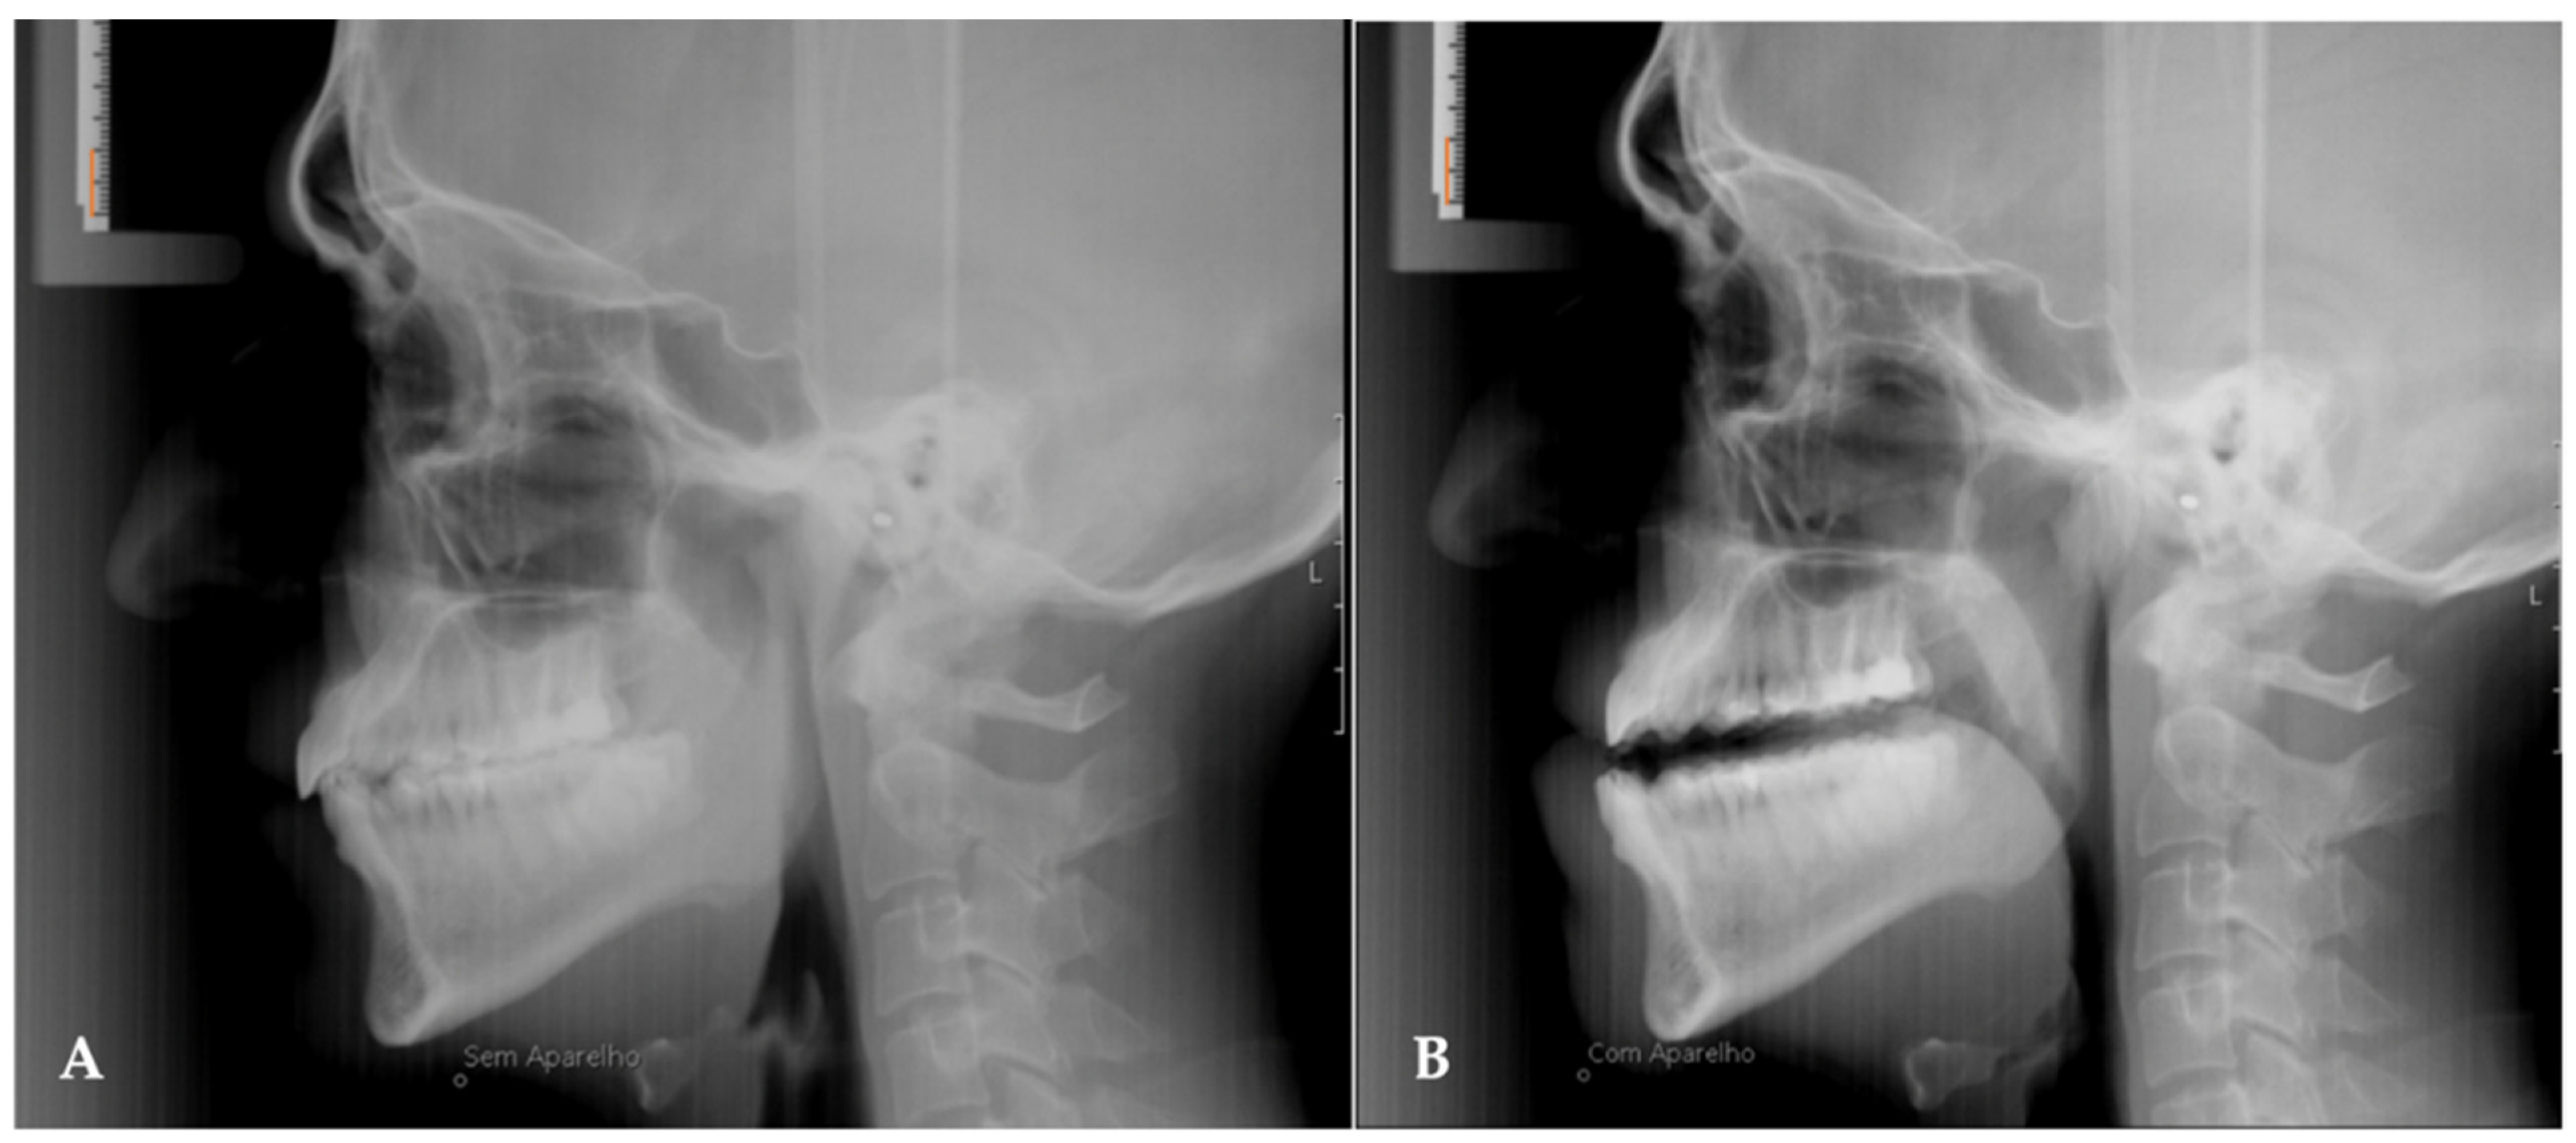

In all patients, two lateral cephalograms were taken, one before starting treatment (T0) and the other after 1 year of treatment (T1). In the final teleradiography (T1) the patients had the MAD placed intra-orally (Figure 2). Moreover, during the evaluation of the results, all patients underwent cardiorespiratory study polysomnography (AASM level III).

Figure 2. Teleradiography without the device in place (A) and teleradiography one year after treatment with the device in place (B). The orange line measures 10 mm.